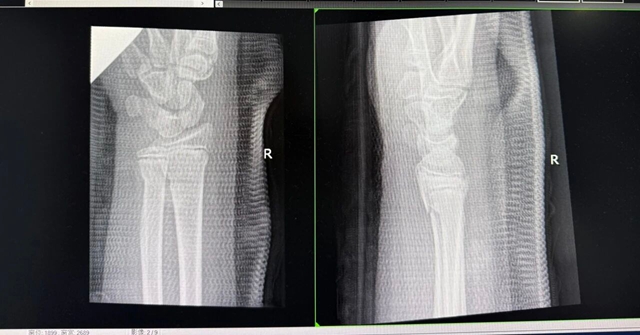

立即复查X片,骨折对合良好,复位成功!兴奋之余,医生和家属也松了口气,但都略显疲惫,而此时已是凌晨2点。

复位后

俗话说“伤筋动骨一百天”,小丽在医院经过细致的中医康复治疗后肿胀已完全消退、感觉也恢复了,目前已康复出院,但治疗尚未结束,后期还需门诊复查。